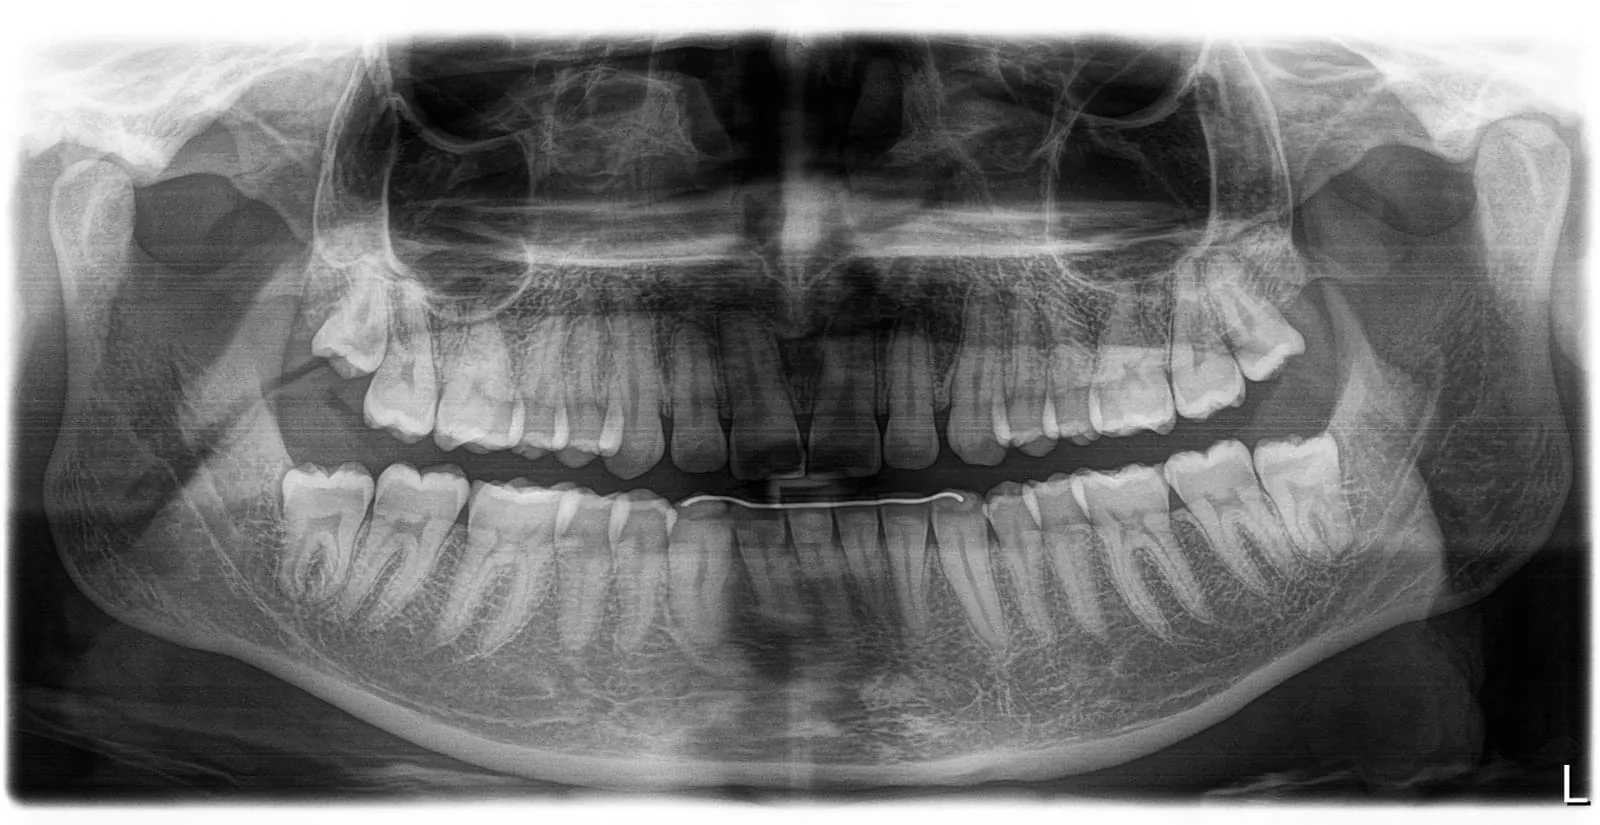

Radiografia Panorâmica

A radiografia panorâmica é um exame de imagem que proporciona uma visão ampla de toda a cavidade bucal em uma única tomada, permitindo a avaliação simultânea das arcadas superior (maxila) e inferior (mandíbula), além das estruturas adjacentes.

Por meio deste exame, é possível identificar alterações como lesões cariosas extensas, reabsorções ósseas e radiculares, granulomas, cistos, tumores, dentes inclusos/impactados e fraturas decorrentes de traumas.

Trata-se de um exame extraoral, rápido, confortável e de baixa exposição à radiação, frequentemente solicitado como exame inicial para planejamento de tratamentos, acompanhamento da saúde bucal e como exame pré-operatório.

Radiografia Panorâmica

A radiografia panorâmica oferece uma visão ampla e completa de todas as estruturas bucais em uma única imagem. Fundamental para avaliação odontológica geral.

Qual a diferença entre radiografia periapical e panorâmica?

A radiografia periapical é intraoral e mostra de 1 a 4 dentes em alta definição, sendo ideal para diagnóstico de canais, lesões cariosas e granulomas.

A panorâmica é extraoral e mostra todas as arcadas, mandíbula, maxila e ATM em uma única imagem, sendo usada para visão geral, planejamento ortodôntico e identificação de dentes inclusos.